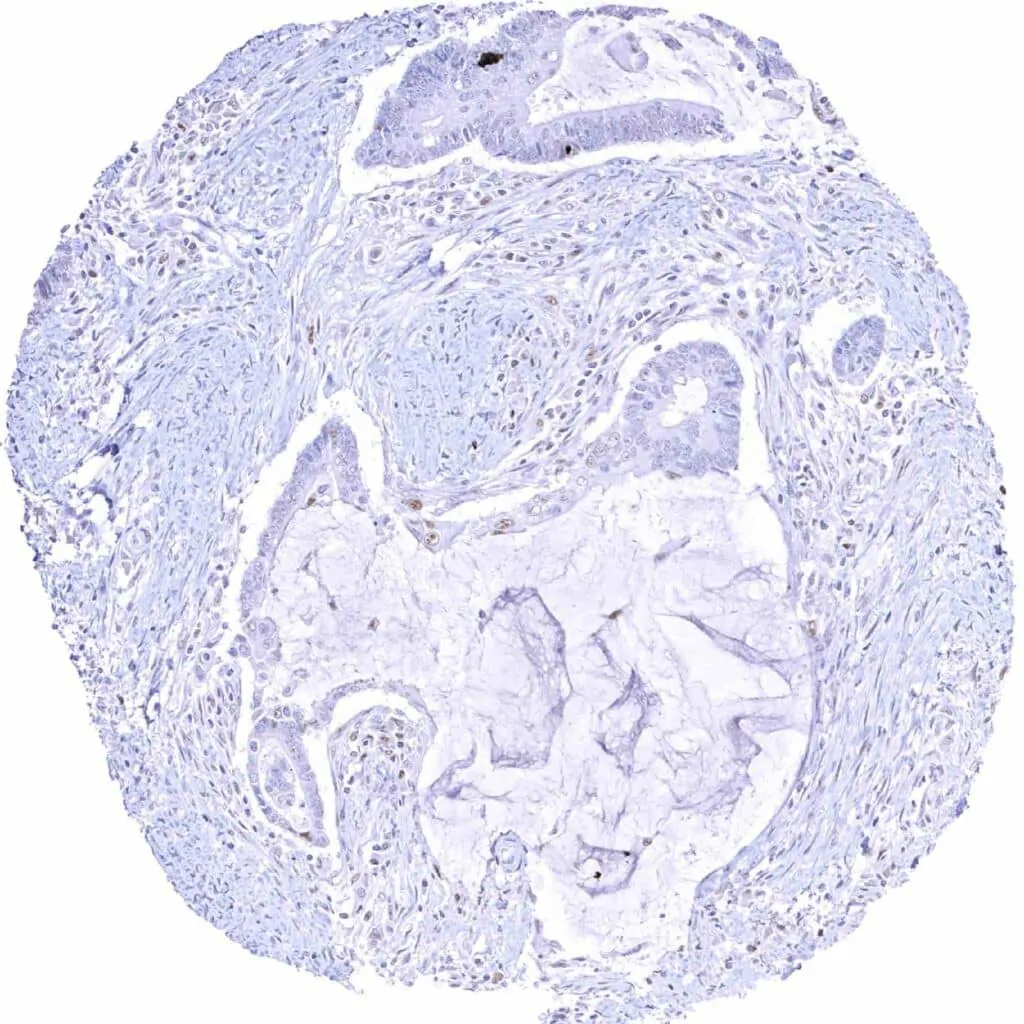

Pharynx – Squamous cell carcinoma with a weak to moderate Cyclin E1 staining of a subset of tumor cells